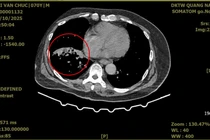

Ngày 11/11, Bệnh viện Đa khoa Trung ương Quảng Nam thông tin, một người đàn ông 70 tuổi ở xã Núi Thành, TP Đà Nẵng đã được đơn vị cứu sống sau khi rơi vào hôn mê sâu vì ho ra máu nặng nguyên nhân từ phổi, nhờ phát hiện sớm và xử trí kịp thời.

Bệnh nhân là ông Bùi Văn Ch. (70 tuổi, trú tại xã Núi Thành, TP Đà Nẵng) được người nhà đưa đến bệnh viện vào đêm 26/10 trong tình trạng hôn mê, khó thở, ho ra máu nhiều, gây suy hô hấp nặng. Kết quả đo cho thấy nồng độ oxy trong máu động mạch (SpO₂) chỉ còn 65%.